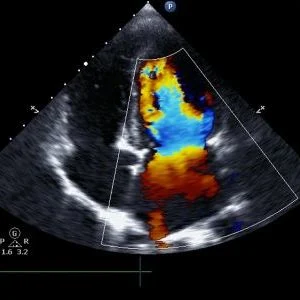

Atrial myopathy is a condition characterized by abnormal left atrial function and size. Since lower left atrial reservoir function is associated with silent brain infarcts and white-matter hyperintensities, the research team examined if poor left atrial function and size is associated with dementia.

About 4,096 subjects (mean age of 35 years, 60% women) originating from the Atherosclerosis Risk in Communities (ARIC) study participated in this study. Of the participants, 531 developed dementia over a six-year period. Worse left atrial function as determined by echocardiography, but not size, was associated with a higher risk for dementia. Specifically, dementia development in the lowest quintile of left atrial function measures (reservoir strain, conduit strain, and contractile strain) was 1.5 to 2.0-fold higher that of the highest quintile. Cardiovascular disease, atrial fibrillation, and common measures of left atrial size were not significantly associated with dementia.

The study authors conclude that impaired left atrial heart function may be a risk factor associated with dementia. In an accompanying editorial, Dr. Shyam Prabhakaran from the University of Chicago and Dr. Philip Greenland from Northwestern University wrote that given the 'given the exploratory nature of the study findings, prospective validation in other cohorts is clearly necessary' and that a casual link may be established given randomized clinical trials testing treatment of impaired left atrial heart function.